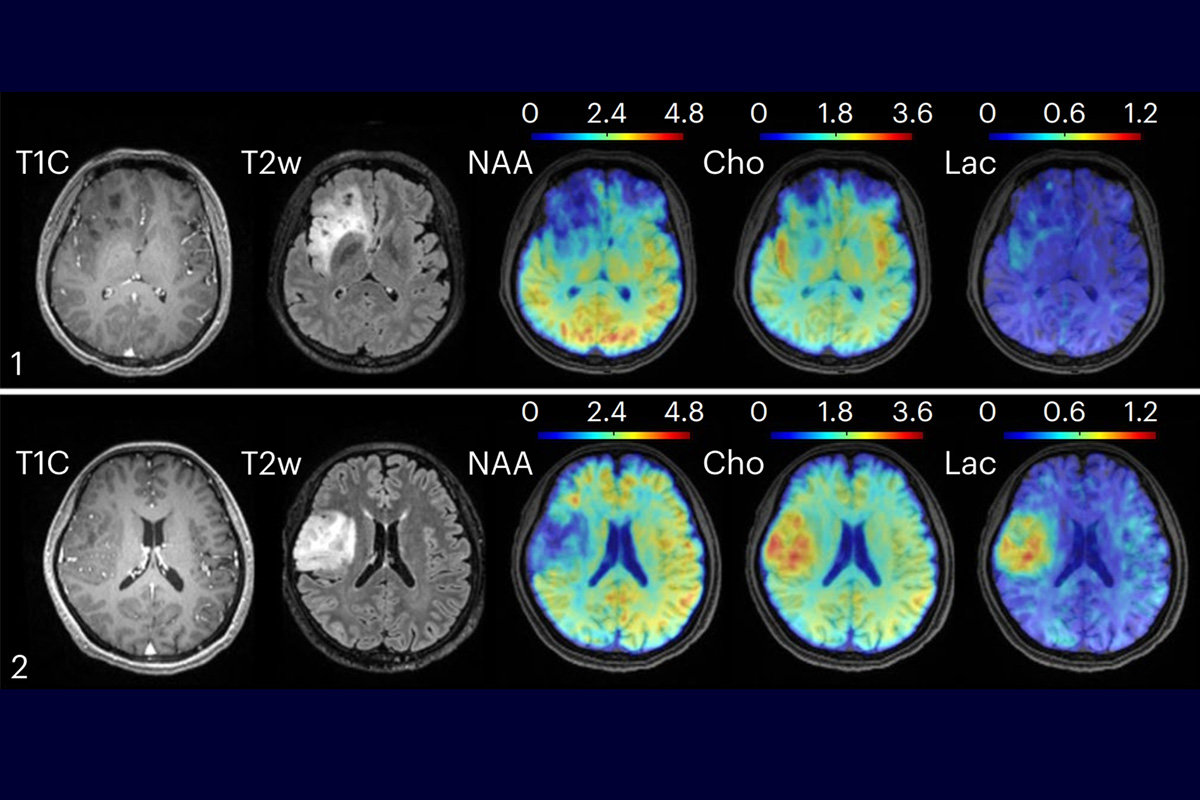

Zhi-Pei Liang is leading research at the intersection of artificial intelligence and magnetic resonance imaging of the brain. The lab's non-invasive, high-resolution metabolic imaging of the whole brain revealed differences in metabolic activity and neurotransmitter levels among brain regions. Liang's team found metabolic alterations in brain tumors. Team members mapped and characterized multiple sclerosis lesions, while patients spent only minutes in an MRI scanner.

“Our technology overcomes several long-standing technical barriers to fast high-resolution metabolic imaging by synergistically integrating ultrafast data acquisition with physics-based machine learning methods for data processing,” Liang said in a release about the work. With the new MRSI technology, the Illinois team cut the time required for a whole brain scan to 12 and a half minutes."

In subjects with multiple sclerosis, the technique detected molecular changes associated with neuroinflammatory response and reduced neuronal activity up to 70 days before changes become visible on clinical MRI images.